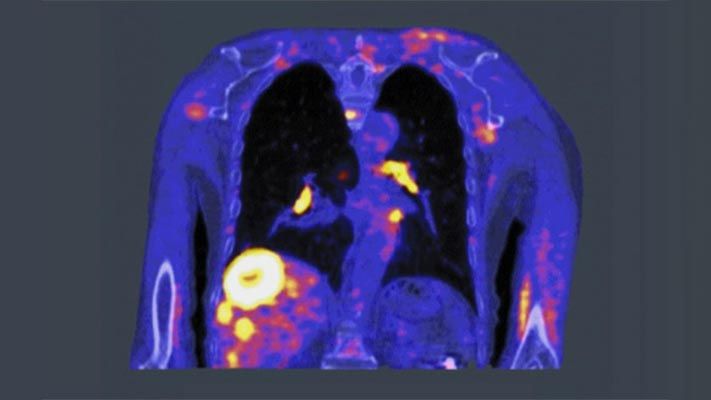

Vous pouvez utiliser la médecine in silico pour développer de nouveaux équipements médicaux avec MATLAB et Simulink. Vous pouvez créer des modèles physiologiques fonctionnels d'organes humains tels que les poumons, les reins, le pancréas, le cœur et le système cardiovasculaire pour répliquer de manière adéquate l'anatomie et la physiologie du corps humain. Ces modèles peuvent alors être utilisés pour la validation des designs et l'évaluation clinique des performances de nouveaux équipements thérapeutiques. Cela permet aux fabricants de raccourcir le cycle de développement produit sans compromettre la qualité ou la sécurité.